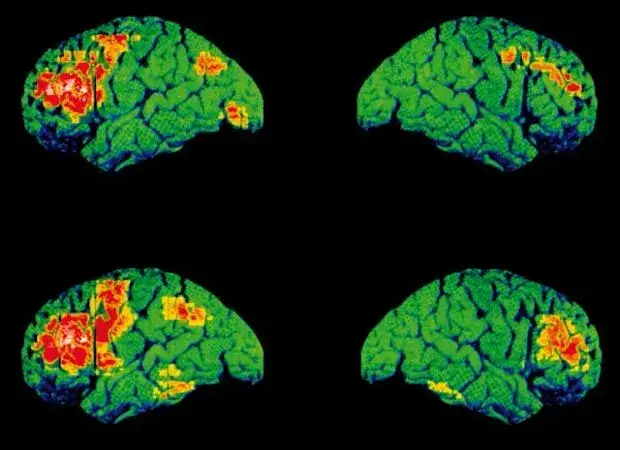

- Mit o depresji: "Depresja to tylko zwykły smutek, lenistwo albo wymówka, żeby nic nie robić." * Fakt: Depresja to poważna choroba mózgu, która wpływa na chemię neuroprzekaźników, zaburzając nastrój, energię, sen, apetyt i zdolność do odczuwania przyjemności. To nie jest kwestia woli czy charakteru, a stan, który wymaga profesjonalnego leczenia.